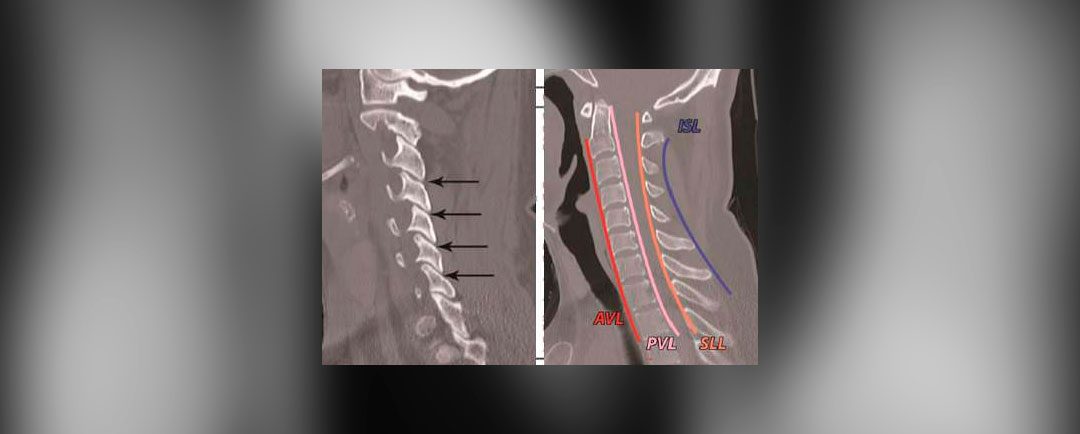

por Dr. Esteban Castro | Nov 21, 2020 | Columna, Cuello

Esguince cervicalQuién puede tratar o diagnosticar la enfermedad o padecimiento:Medios de diagnóstico:Tiempo de recuperación:Síntomas:Tratamientos:Cuidado y apoyo: Lesiones en el cuello por movimientos bruscos de extensión y flexión. Esguince cervical Lesiones de los...